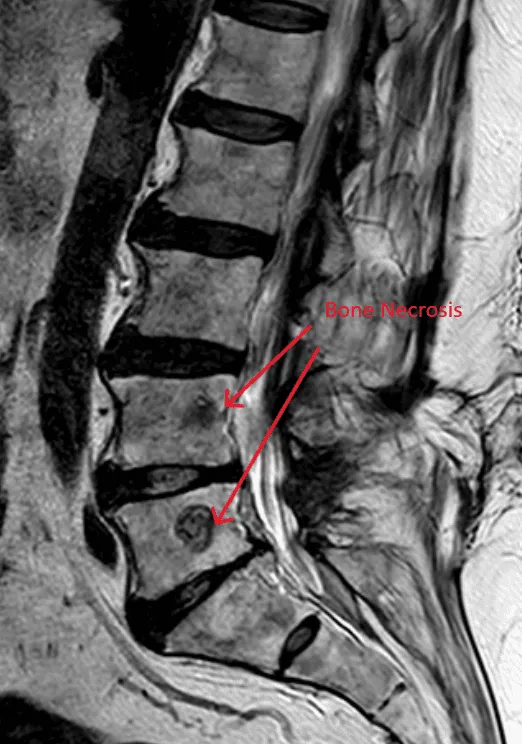

MRI of the lower spine highlighting bone necrosis with red arrows.

Bone Necrosis (Bone Death)